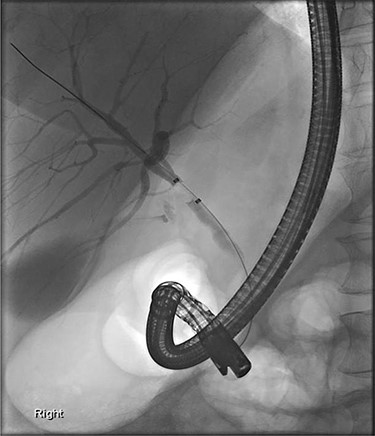

Further examination led to a diagnosis of DCBD with a separate left intra- and extrahepatic bile duct with ectopic drainage into the stomach. Magnetic resonance cholangiopancreatography (MRCP) revealed marked left intrahepatic duct (IHD) dilatation. The left IHDs were draining via an aberrant extra-hepatic bile duct into the pre-pyloric region. The left and right hepatic ducts did not communicate. It also demonstrated pancreatic divisum and multiple side branch intra-ductal papillary mucinous neoplasms (IPMN) (Fig. 3). Endoscopic retrograde cholangiopancreatography (ERCP) confirmed the MRCP findings but also revealed an intraluminal-filling defect in the left IHD (Figs 4 and 5).

ERCP: cannulation via the pre-pyloric fistula opening. Contrast outlining the ACBD and the left IHDs.